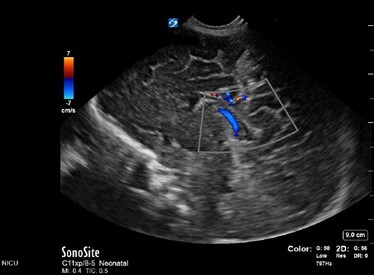

Neonatology Normal Anatomy Low Velocity Image